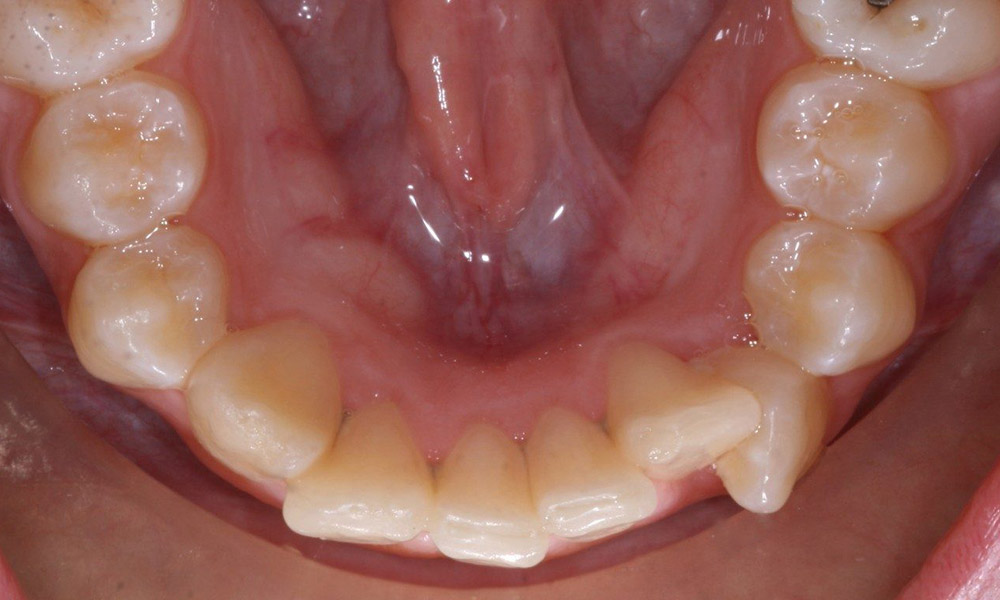

فشردگی یا نامرتبی

اگر دندان عقل فضای کافی برای بیرون آمدن نداشته باشد، میتواند به دندانهای دیگر فشار وارد کند و باعث شلوغی یا جابجایی شود. این میتواند بر روی گاز گرفتن شما تأثیر بگذارد و جویدن را دشوار کند.

اگر دندان عقل شما احتمالاً دندانهای شما را نامرتب میکند یا در کار ارتودنسی اختلال ایجاد میکند، دندانپزشک ممکن است کشیدن دندان عقل را پیشنهاد کند.

به هم ریختگی ساختار دندان ها بر اثر باقی ماندن دندان عقل